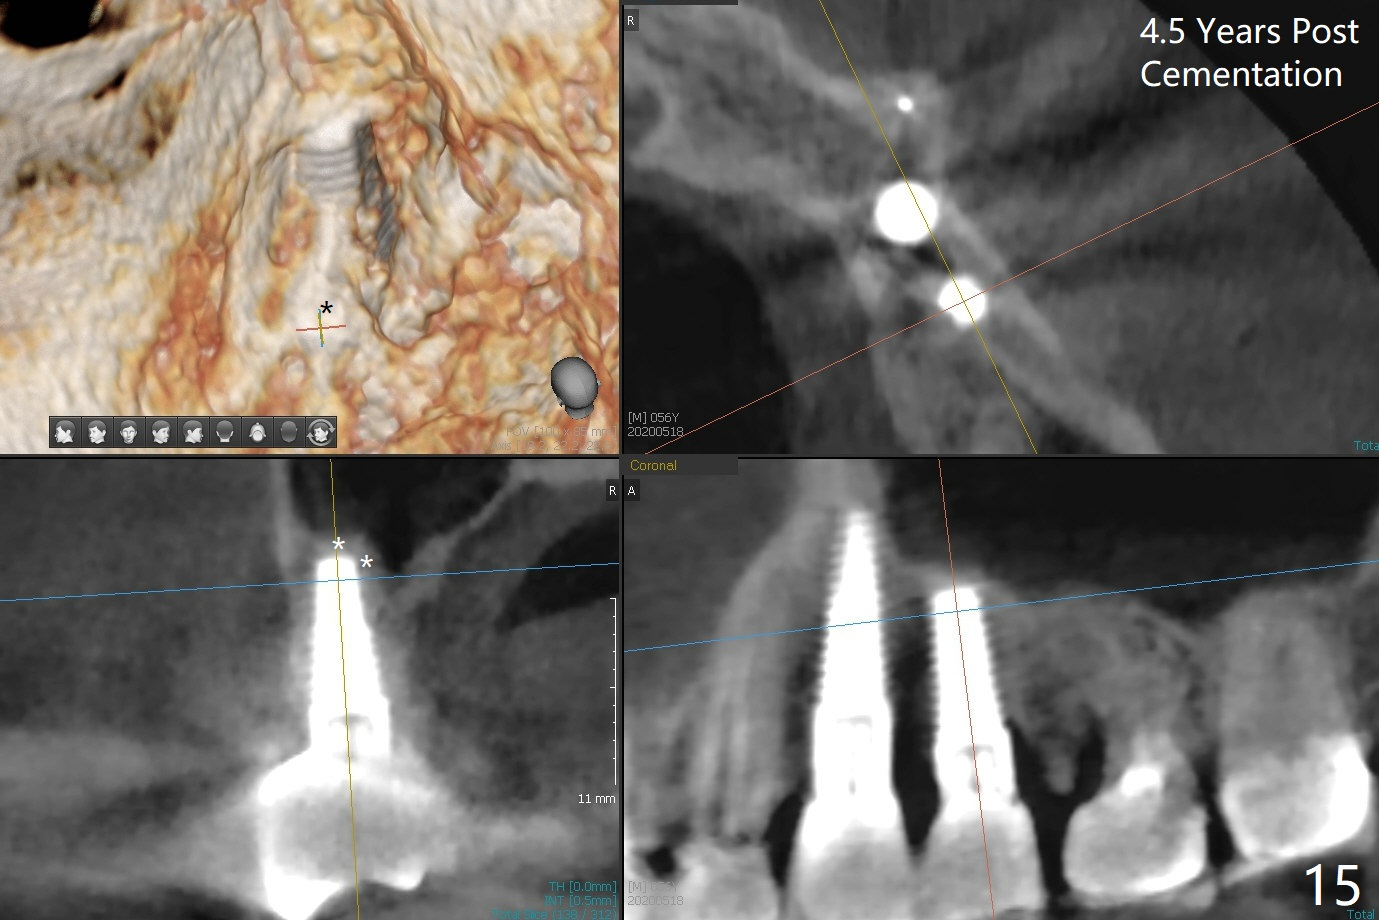

The distal threads appear not covered by the bone 2.5 months postop (Fig.11 >). His oral hygiene is excellent with healthy gingiva around the implant when the permanent crown is cemented. Panoramic X-ray is taken 3 years and 1 year 5 months post cementation for #12 and 13, respectively (Fig.12). The bone density around the implant at #13 increases 2 years 6 months post cementation (Fig.13 *). The bone density of the sinus lift (Fig.14,15 *) is essentially the same as that of the bone buccal (B) and palatal to the implant 4.5 years post cementation. The upper left panel is a 3D view from the sinus.